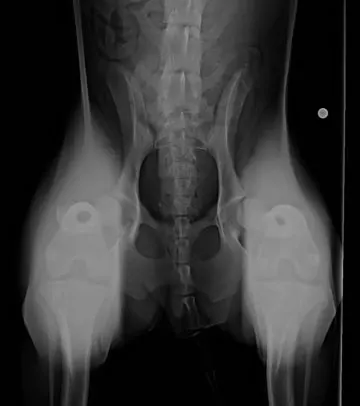

- Distraction ventrodorsal or dorsoventral view to assess joint laxity (Figure 3): - PennHIP (requires certification of the veterinarian) or dorsolateral subluxation score18

(Right) Ventrodorsal distraction view of the 10-month-old Australian shepherd in Figure 2. The dog’s femurs were held perpendicular to the radiography table and pressure was applied to luxate the coxofemoral joint dorsally. Note the laxity and luxation of the femoral heads from the acetabulum bilaterally. Significant bone remodeling and osteophytes are present in the left acetabulum. (view larger image)